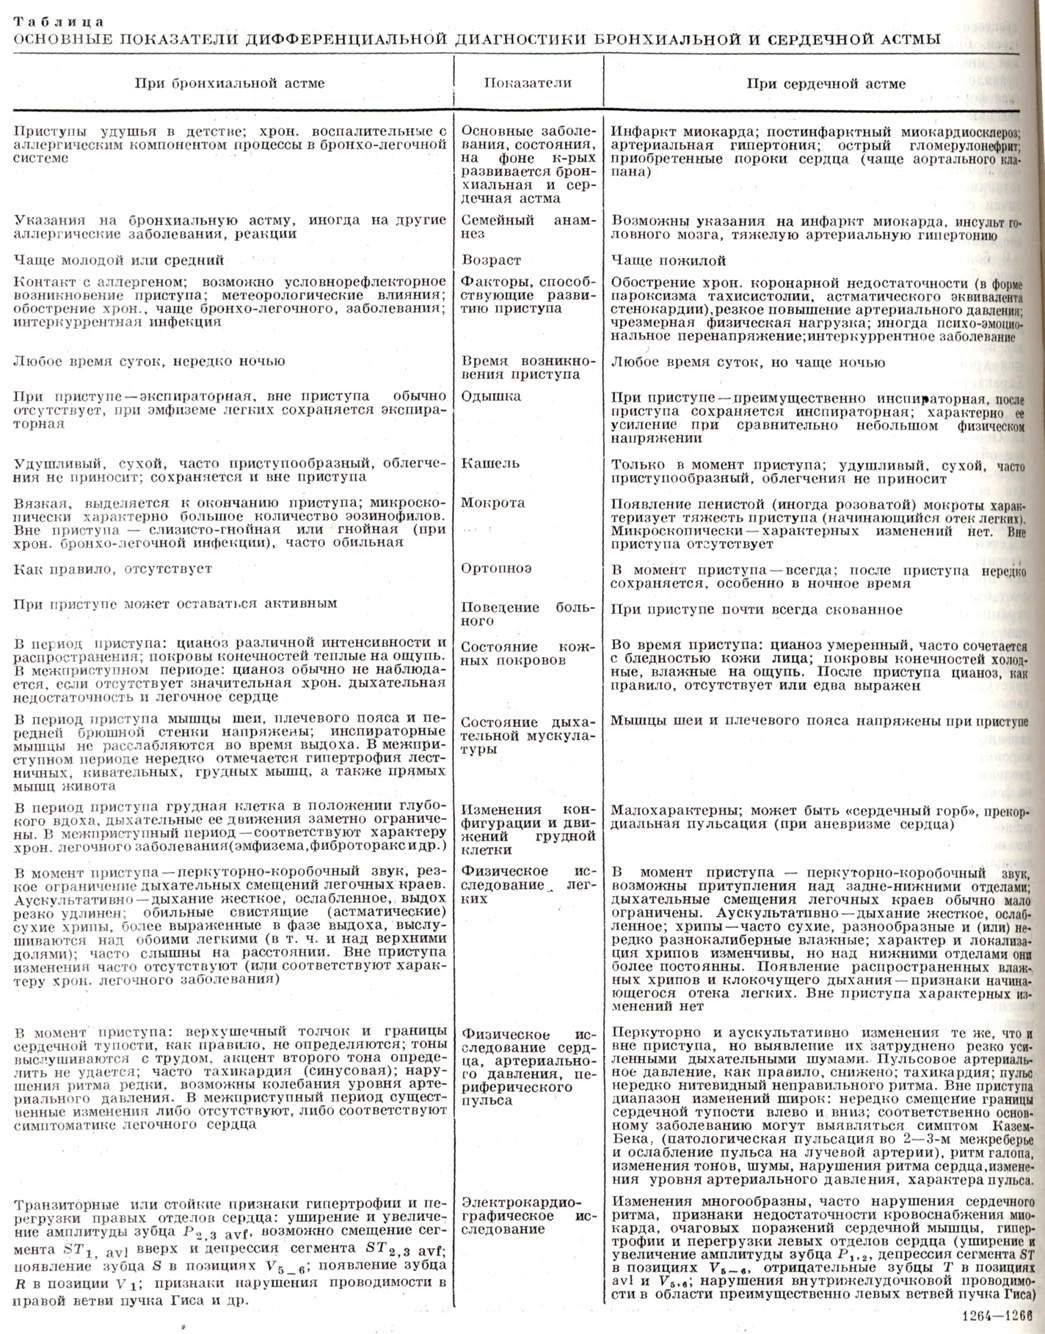

Часто Б. а. необходимо дифференцировать с сердечной астмой (см. табл. Основные показатели дифференциальной диагностики бронхиальной и сердечной астмы). Важным моментом в дифференциальной диагностике является анамнез. Указания на артериальную гипертонию, коронарную недостаточность, перенесённый инфаркт миокарда, клапанные поражения сердца, а также отмечаемые при объективном исследовании увеличенные размеры сердца и печени, отеки и другие симптомы говорят в пользу сердечной астмы (см.). Особенно труден дифференциальный диагноз, когда при Б. а. наступает декомпенсация по правожелудочковому типу.